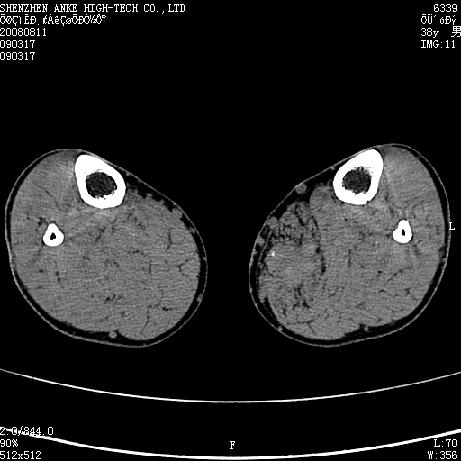

标题: CT15117:M38Y,小腿平扫 [打印本页]

标题: CT15117:M38Y,小腿平扫

患者,男,38岁,右小腿疼痛性包块1月,查体:右小腿可扪及约5x4cm大小包块,压痛.

左小腿内侧软组织病变,性质待定(血管瘤?);建议行mri检查。